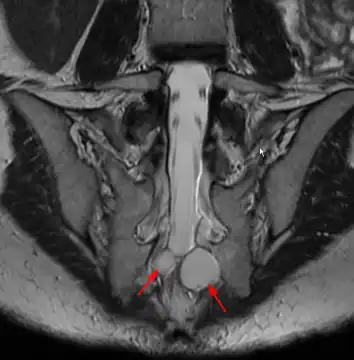

MRI image showing a Tarlov cyst

MRI sagittal image of sacral and dorso-lumbar perineural cysts.

MRI

MRI, or Magnetic Resonance Imaging, is considered the imaging study of choice in identifying Tarlov cysts. MRI provides better resolution of tissue density, absence of bone interference, multiplanar capabilities, and is noninvasive. Plain films may show bony erosion of the spinal canal or of the sacral foramina. On MRI pictures, the signal is the same as the CSF one.